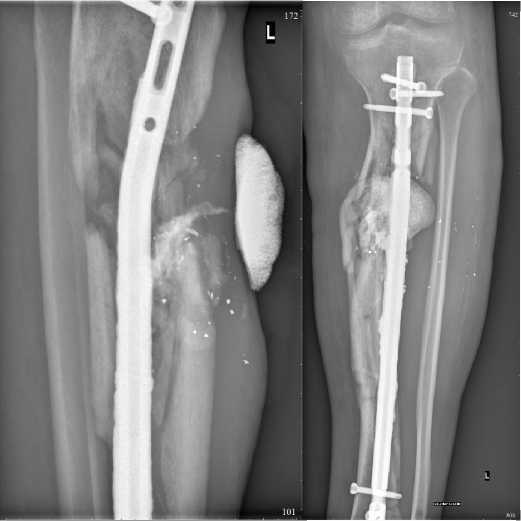

Рисунок 3. Рентгенограмма области плеча при поступлении без фиксации многооскольчатого фрагментарного перелома средней и дистальных третей диафиза плечевой кости со смещением (а), после выполнения остеосинтеза стержневым аппаратом внешней фиксации (б), после выполнения остеосинтеза накостной пластиной на 8-ми винтах, с минимальным смещением в стадии консолидации (в) Figure 3. Radiograph of the shoulder area upon admission without fixation of a multi-fragmentary fragmentary fracture of the middle and distal thirds of the humerus diaphysis with displacement (a), after osteosynthesis with an external fixation rod apparatus (б), after osteosynthesis with an 8-screw bone plate, with minimal displacement in the consolidation stage (в)

Рисунок 4. Рентгенограммы использования методики последовательного остеосинтеза многооскольчатого перелома верхней трети диафиза левой плечевой кости, а – выполнен стержневой остеосинтез, б – выполнен остеосинтез интрамедуллярным винтом

В большинстве случаев на этапе оказания специализированной помощи использовали последовательное выполнение различных видов остеосинтеза (рис. 3, 4) с сопровождением каждого метода фиксации рентгенографическим исследованием.